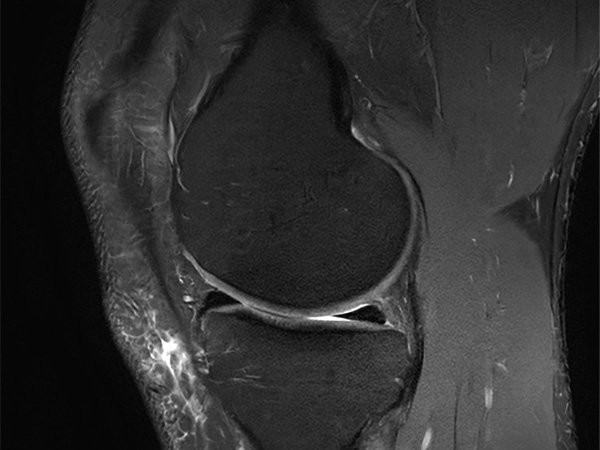

Fast Knee imaging with SmartSpeed Precise

• Clinical Application